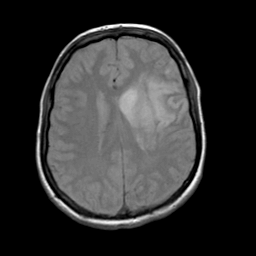

Acute Stroke: proton density-weighted MR -- Slice #16

[Home][Help][Clinical][Tour 1] Slice 16